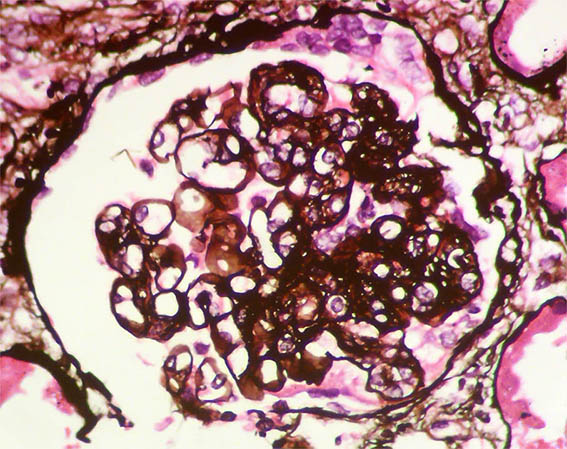

Figura 8. Plata-metenamina, X400. Patrón de membranoproliferativa y pequeña semiluna en la parte superior.

Figura 9. Plata-metenamina, X400. Dobles contornos. Mitosis, posiblemente de un podocito, en la parte superior.